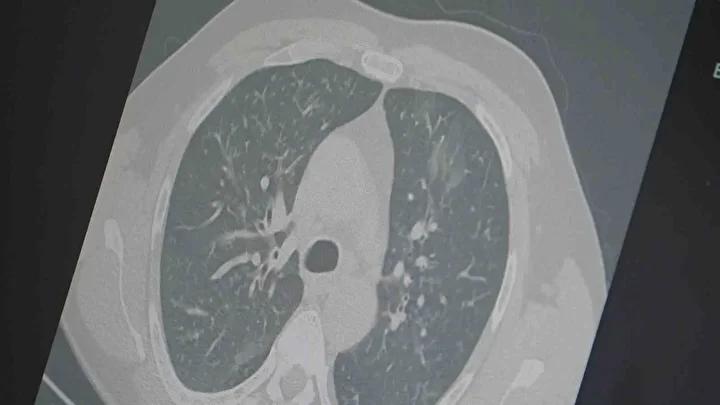

Sonbahar ve mevsim geçişleriyle birlikte solunum yolu enfeksiyonlarında yeniden artış yaşanıyor. Uzmanlar, grip, COVID-19 ve RSV virüslerinin aynı dönemde yayılmasıyla ‘üçlü salgın’ riskine dikkat çekiyor. Hava sıcaklıklarında ani değişiklikler bağışıklık sistemini zayıflatırken, bu durum enfeksiyonların yayılma hızını artırıyor.

Göğüs Hastalıkları Uzmanı Prof. Dr. Şevket Özkaya, mevsimsel değişimlerin bağışıklık direncini düşürdüğünü ve bunun da enfeksiyonları uzattığını belirtiyor. Bu süreçte, virüslerin özellikle hızla yayılan yeni varyantlarıyla karşılaşmak mümkün oluyor. Türkiye’de son zamanlarda tespit edilen “Frankenstein varyantı” adını alan yeni tür, salgını daha ciddi hale getirebilir.

Prof. Dr. Özkaya, yeni varyantın Türkiye’de de görüldüğünü ifade ederek, “Mevcut klinik tabloda kritik veya yaşamı tehdit eden durumlar henüz oluşmadı. Ancak bu varyantın bulaşıcılığı çok yüksek ve Avrupa ile Asya’da hızlı bir şekilde yayılıyor,” diye konuştu.

Uzmanlar, grip ve COVID-19’un, özellikle tedavi edilmediğinde veya iyileşme sürecinde zatürreye dönüşme riskinin yüksek olduğunu belirtiyor. Dr. Özkaya, “Hastalıklar akciğerlere inip ciddi solunum problemlerine yol açabiliyor, bu da hastaneye yatış oranlarını artırıyor,” diyerek uyarıda bulunuyor.

Salgının, günlük yaşamı çok fazla aksatmamasına rağmen, dikkat edilmezse hızla yayılmaya devam ettiği vurgulanıyor. “Virüsler, hastalanmadan ya da tam iyileşmeden toplumda dolaşmaya devam ediyor. Dinlenmeden ve izolasyon uygulamadan enfekte kişiler, enfeksiyon zincirini sürdürüyor,” diyor Prof. Dr. Özkaya.

Doktorlar, vatandaşlara herhangi bir grip benzeri belirti fark edildiğinde evde dinlenmeyi öneriyor. Ayrıca, öksürük ve nefes darlığı gibi belirtilerde mutlaka sağlık kuruluşlarına başvurulması önemli. Uygun tanı ve tedavi alarak, ciddi komplikasyonların önüne geçmek mümkün oluyor.